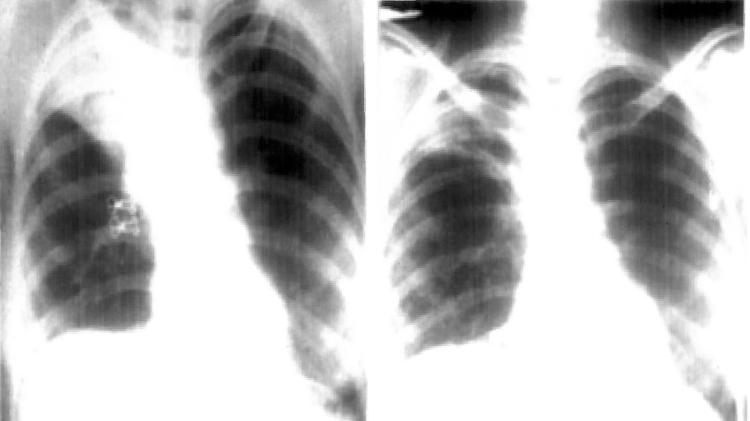

Camisinha foi encontrada em pulmão de professora de 27 anos, na Índia – Foto: Reprodução/C. L. Arya, R. Gupta, V. Arora/Semantic ScholarCamisinha foi encontrada em pulmão de professora de 27 anos, na Índia – Foto: Reprodução/C. L. Arya, R. Gupta, V. Arora/Semantic Scholar

Depois de exames para confirmar a doença, os médicos perceberam que havia uma lesão em um lobo pulmonar superior da professora, resultado da inalação do preservativo. O teste para tuberculose deu negativo. Assim, os especialistas examinarem o tórax da paciente e notaram “estrutura semelhante a uma bolsa invertida ‘parada’ no brônquio”.